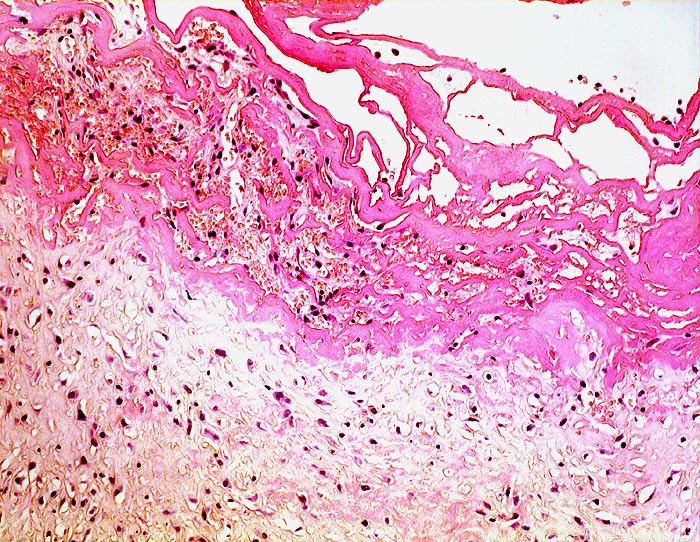

PathoPic – image database / PathoPic ID 4501 - chronische Bursitis mit akutem fibrinösem Schub

chronische Bursitis mit akutem fibrinösem Schub

Mehrere Fibrinschichten bedecken die Bursainnenseite. Das Fibrin wird organisiert durch Granulationsgewebe und wird auf diese Weise in die Bursawand integriert. Innerhalb des Organisationsgewebes finden sich frische Einblutungen.

Vorübergehende verstärkte mechanische Belastung oder Scherkräfte führen zu wiederholter Fibrinexsudation in das Bursalumen und zu Einblutungen.